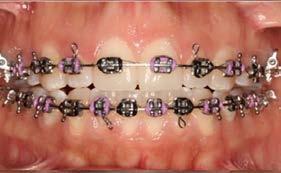

Objetivo: presentar un caso clínico de paciente con mordida abierta anterior, clase II y deglución atípica tratada con aparatología fija ortodóntica.

Caso clínico: paciente femenino de 19 años, patrón dolicofacial, perfil convexo, clase II esqueletal debido a una retrusión mandibular, mordida abierta anterior esqueletal, clase II molar, clase canina no establecida por mordida abierta, apiñamiento severo superior e inferior y deglución atípica.

Resultados: obtención de una clase canina I y clase molar II funcional, se corrigieron las sobremordidas horizontal y vertical, y se logró la coincidencia de líneas medias facial y dental. El manejo de la mordida abierta anterior se llevó a cabo por medio de la corrección del hábito de deglución atípica con la ayuda de spikes de resina, elásticos intermaxilares y arcos utility, y se obtuvieron buenos resultados estéticos, dentales y funcionales.